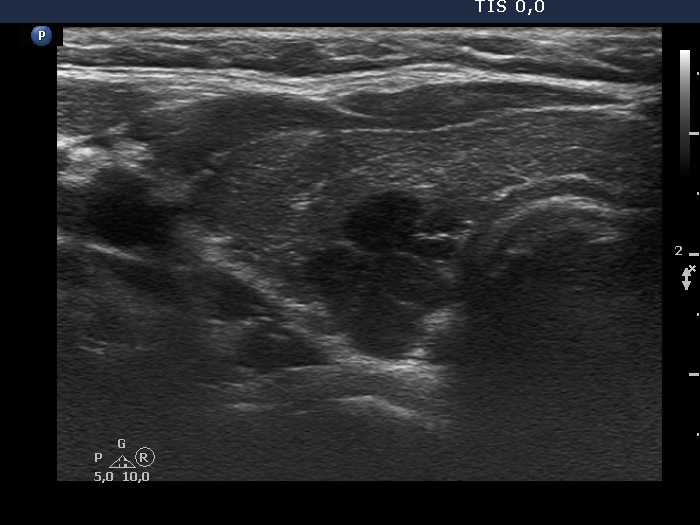

Ultrasonography. The thyroid was minimally hypoechogenic and had several discrete more hypoechogenic areas, including a cluster composed of multiple discrete lesions in the dorsal part of the left lobe. These lesions had irregular, partly lobulated, partly spiculated margins. However, the entire pattern corresponded to Hashimoto's thyroiditis.

Regarding the nodule borders the lesions presented partly lobulated, partly spiculated margins. However, these should not be held as pathological nodules, the discrete lesions are presentations of more active foci of Hashimoto's thyroiditis, which is an infiltrative process and therefore frequently has infiltrative, irregular margins.